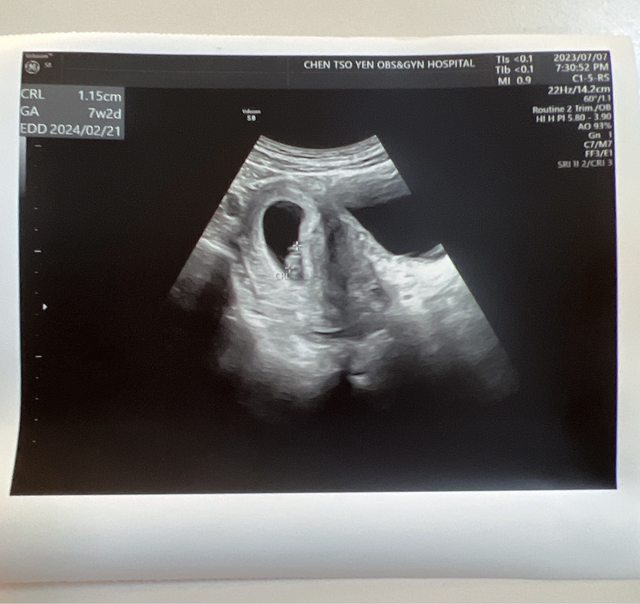

至於大心啊 我和內人即將迎來一位新成員 正式從歐兔畢業囉 https://i.imgur.com/l7y2qXu.jpg